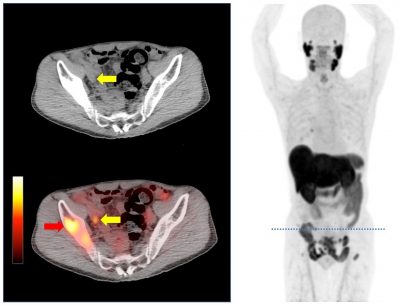

- 前立腺がんの特異的抗体を用いたPET診断に関する臨床研究を国内で初めて開始。初回の検査を実施し、従来よりも高精度で再発・転移巣を検出することを確認。

大阪大学医学部附属病院(以下、阪大病院)は、本年9月より前立腺がんの高精度画像診断であるF-18 PSMA-1007 PET臨床研究 *1を国内で初めて開始しました。9月3日に初回のPSMA-PET検査が問題なく実施され、CT や骨シンチ*2といった従来の画像診断では同定できなかった再発・転移巣が検出できることが分かりました。PET検査薬は加速器(サイクロトロン)と標識合成装置(医療機器)を用いて院内で製造されますが、PSMA-PET検査薬の標識合成装置は海外製のみとなっていました。

【目的】前立腺がん患者において、F-18 PSMA-1007 PET/CT検査を行い、従来の転移評価検査であるCTや骨シンチグラフィーと比較することで、PSMA-PETによる診断能を評価し、詳細な病態解明を行う